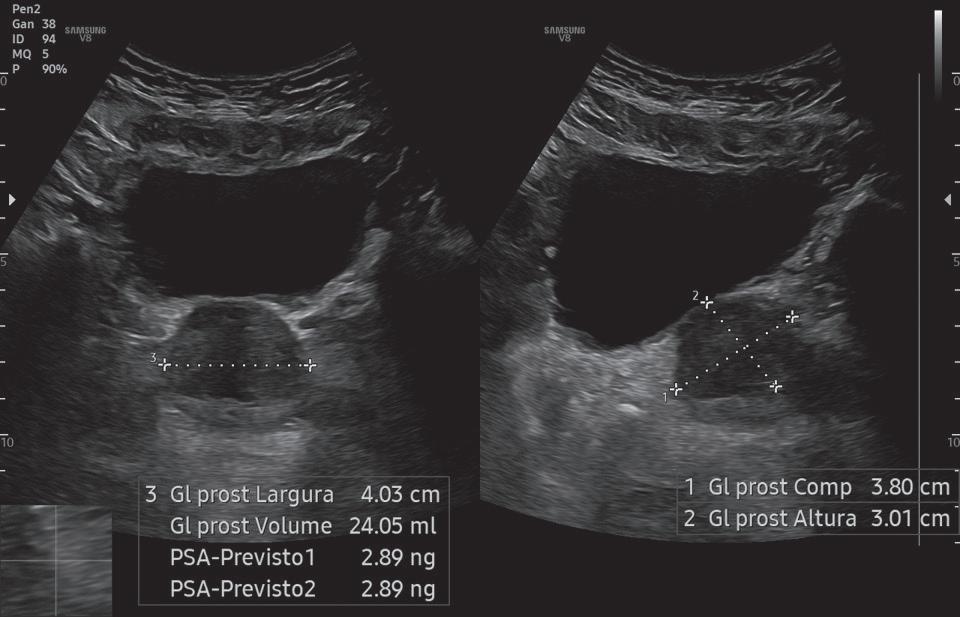

Próstata com peso estimado de ## g.

Fig. 1-8. Medida da próstata.